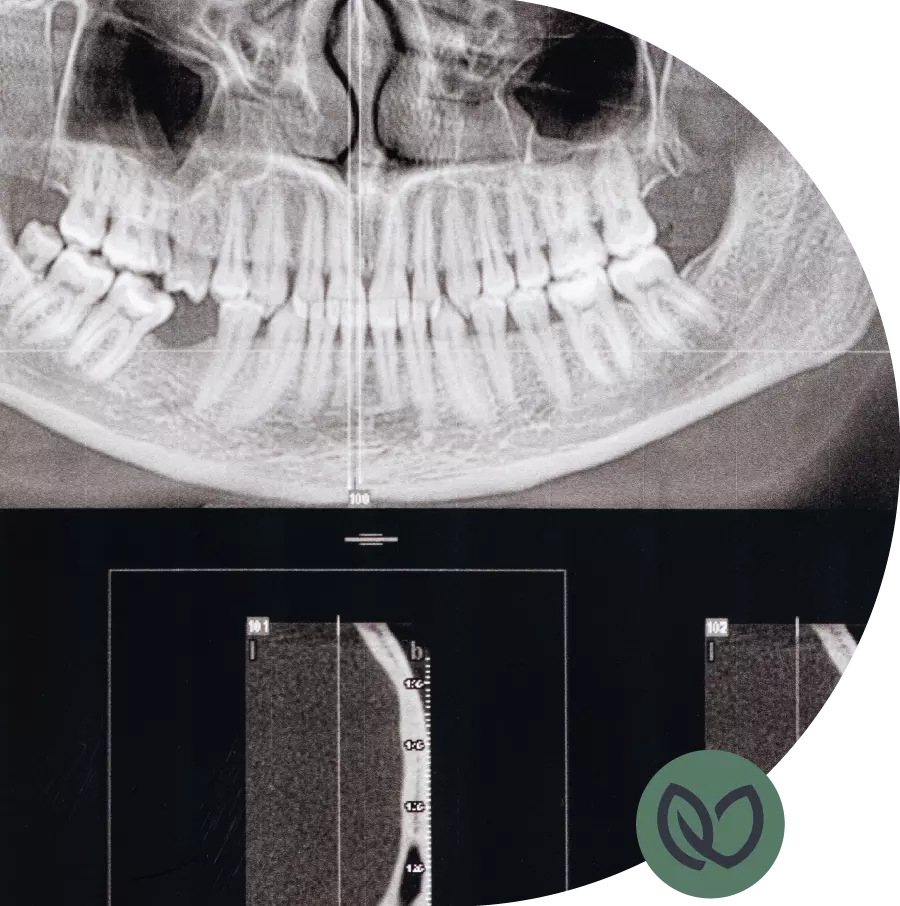

Voordat de tandarts overgaat tot het trekken van de tand of kies, zal hij/zij de nodige röntgenfoto’s maken en uw medische geschiedenis evalueren. Dit helpt bij het bepalen van de beste aanpak en het minimaliseren van mogelijke complicaties. De tandarts zal een lokale verdoving toedienen om het gebied te verdoven en eventueel ongemak te verminderen.

Bij uw intake maakt u persoonlijk kennis met de tandarts in onze praktijk. Tijdens dit eerste bezoek wordt er een uitgebreid mondonderzoek uitgevoerd, waarbij vaak ook foto’s van uw gebit worden gemaakt. Daarna kunt u direct uw eventuele wensen en vragen bespreken met de tandarts.